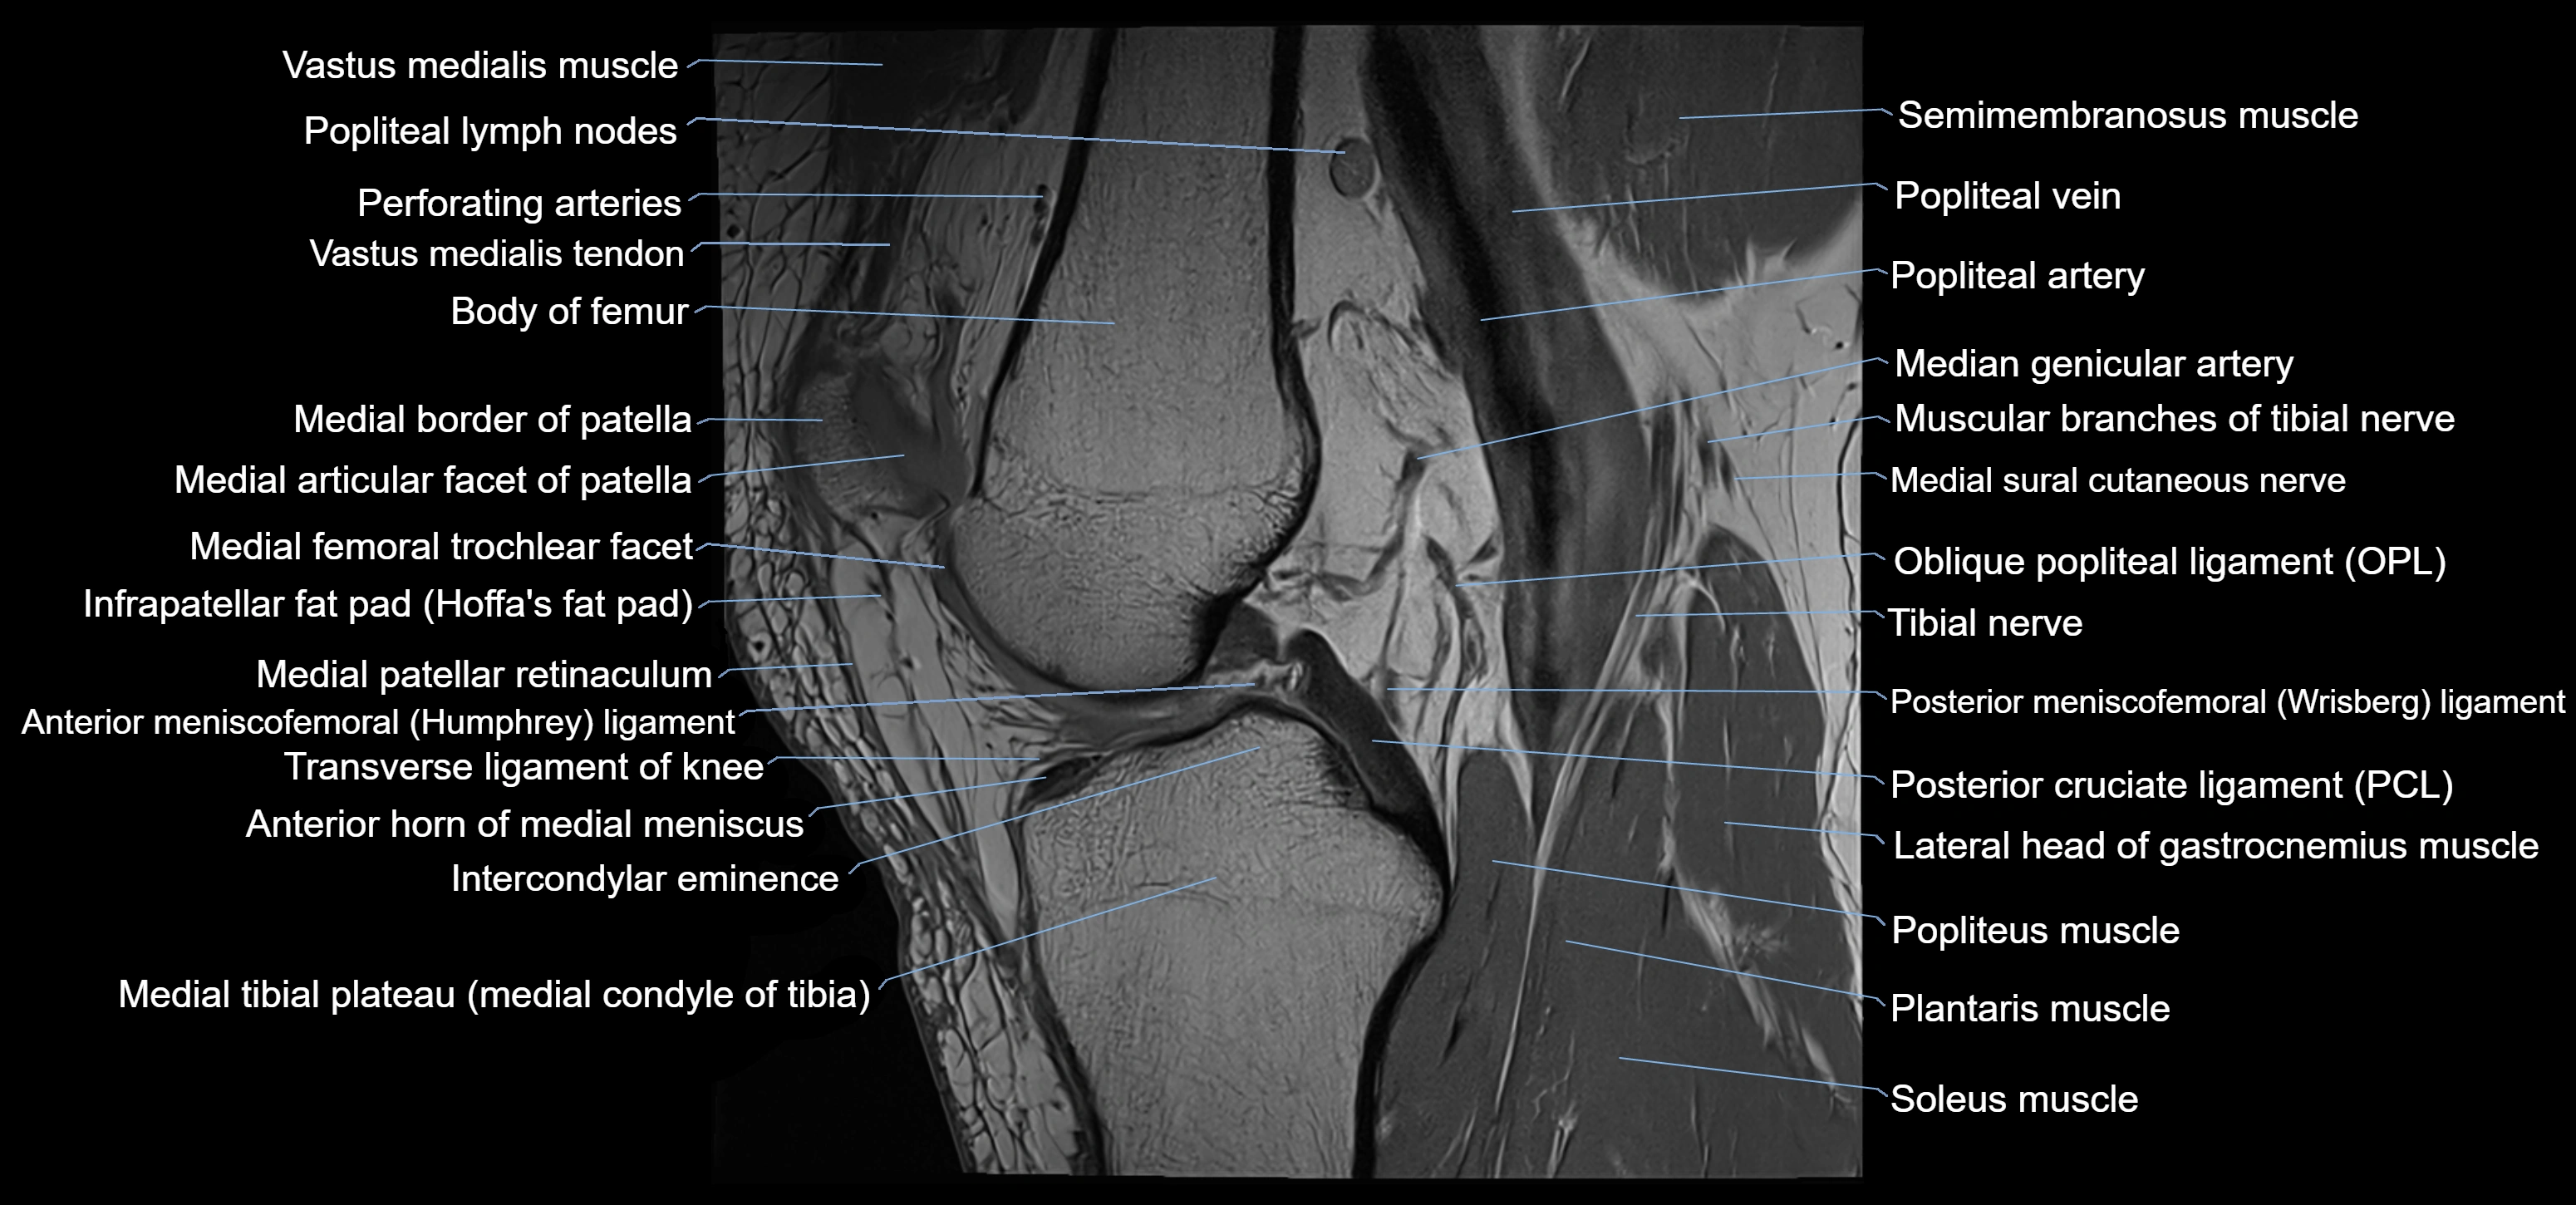

- Anterior horn of medial meniscus

- Anterior meniscofemoral ligament

- Intercondylar eminence

- Lateral head of gastrocnemius muscle

- Medial articular facet of patella

- Medial border of patella

- Medial condyle of tibia

- Medial meniscus

- Medial patellar retinaculum

- Medial tibial plateau

- Muscular branches of tibial nerve

- Oblique popliteal ligament

- Patellar tendon (patellar ligament)

- Popliteal artery

- Popliteal lymph nodes

- Popliteal vein

- Popliteus muscle

- Posterior cruciate ligament

- Posterior meniscofemoral ligament

- Semimembranosus muscle

- Soleus muscle

- Tibial nerve

- Transverse ligament of knee

- Trochlear groove

- Vastus medialis muscle